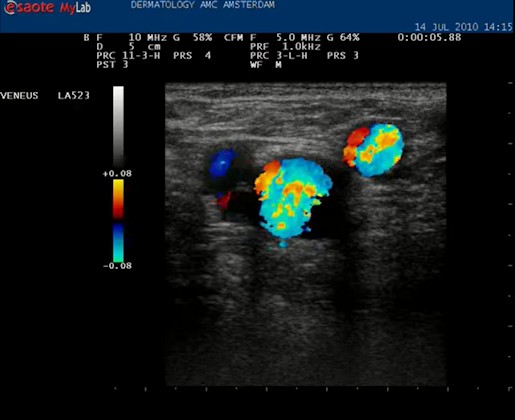

| De volgende stap is om de VSM te vervolgen naar de oorsprong in de lies, daar waar de VSM ontspringt uit de vena femoralis superficialis. Hiervoor proberen we de Mickey Mouse figuur in beeld te krijgen die hier boven te zien is. Vaak verschijnt dat al als de echokop in de liesplooi wordt gezet. Met de markering op de kop naar boven lateraal. Dan is het vat in het midden de vena femoralis. Het linker oortje, kleinere diameter, is de arterie, en het rechter oortje is de vena saphena magna. |

| Anatomie liesplooi. Lichtblauw: vena femoralis, diep systeem. Donkerblauw: vena saphena magna, oppervlakkig systeem. Rood: arteria femoralis. In de liesplooi precies waar de VSM aftakt vormen deze drie vaten de Mickey Mouse figuur. Als de echoknop markering naar lateraal staat is het rechteroortje altijd de VSM. |